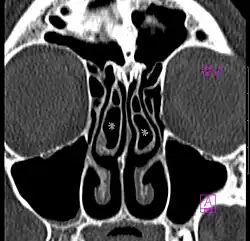

Concha bullosa

La concha bullosa désigne la pneumatisation du cornet nasal moyen[1].

Il s'agit d'une variante anatomique fréquente, retrouvée chez près de la moitié de la population[2]. Elle est bilatérale dans la moitié des cas[2].